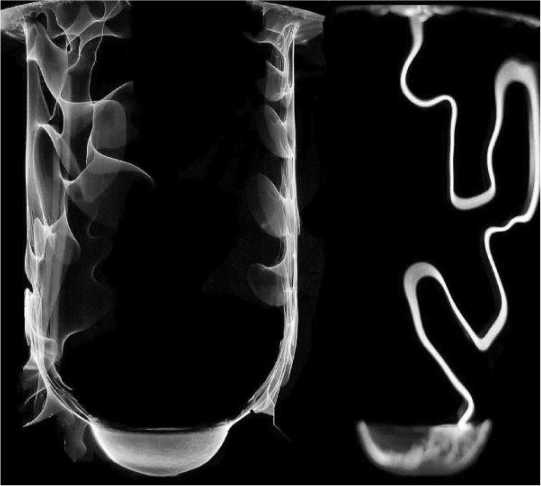

Иллюстрация к книге — Никола Тесла [i_053.jpg]

Электрографические изображения электрической ауры.

Особенно поразили Теслу многочисленные снимки, полученные по оригинальной методике, состоявшей в следующем: один из полюсов вторичной обмотки катушки Румкорфа соединялся с расположенным на высокой башне изолированным от нее металлическим стержнем, направленным в атмосферу, другой — с металлической пластинкой, которая помещалась в пробирку с подкисленной водой. Взяв в руку электрод-пробирку, исследователь другой рукой на мгновение прикасался к светочувствительной пластинке, которая после проявления служила негативом для фотографии.

Однако коллеги Наркевича-Иодко, восхищаясь электрографическими работами автора, не смогли перейти от простого описания уникальных электрографических снимков к их физической интерпретации. И лишь в конце XIX века благодаря исследованиям Николы Теслы стало ясно, что в основе метода электрофотографирования с помощью электрических разрядов лежит явление «естественной эманации лучей корпускулярного электричества», или, говоря современным языком, эмиссия холодных электронов. Сегодня электрофизики считают, что на высокочастотных фотографиях Наркевича-Иодко и Теслы отображались энергетические процессы, изменяющие работу выхода электронов с поверхности растений, животных и человека. При этом разница в работе выхода электронов с различных участков коры или кожи объекта и приводила к неоднородности в распределении эмиссионных токов.

Мы до сих пор точно не знаем, вел ли переписку русский ученый со своим американским коллегой, который пошел несколько иным путем. В самом начале XX века Никола Тесла открыл крайне любопытное явление: если между двумя пластинчатыми электродами, создающими высокочастотное тысячегерцевое электромагнитное поле, расположить какой-нибудь предмет, то он начнет светиться, излучая во все стороны коронный разряд.

Если там же расположить фотопластинку, на ней останется изображение этого предмета в световой ауре. Изобретатель назвал свой метод газоразрядной визуализацией, считая его дальнейшим развитием обычного фотографирования свечения предметов в высокочастотном поле. Проводил ли до Теслы аналогичные эксперименты Наркевич-Иодко, сказать трудно, но вот то, что он первый в мире с помощью своего электрографического метода фиксации коронных разрядов выяснил, что живые организмы дают совершенно иное свечение, чем неживые, сомнения практически не вызывает. Более того, русский ученый настойчиво пытался разработать способ медицинской диагностики по степени свечения человеческих органов, ставя форму охватывающего их ореола в прямую зависимость от внутреннего состояния.